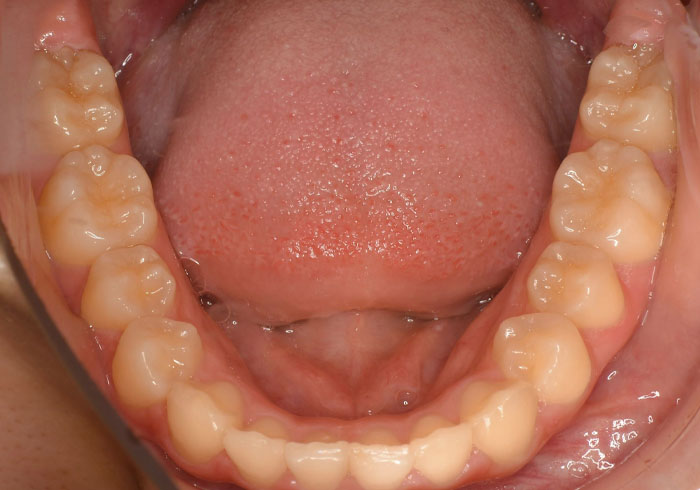

治療前

マウスピース矯正 マウスピース矯正 マウスピース矯正